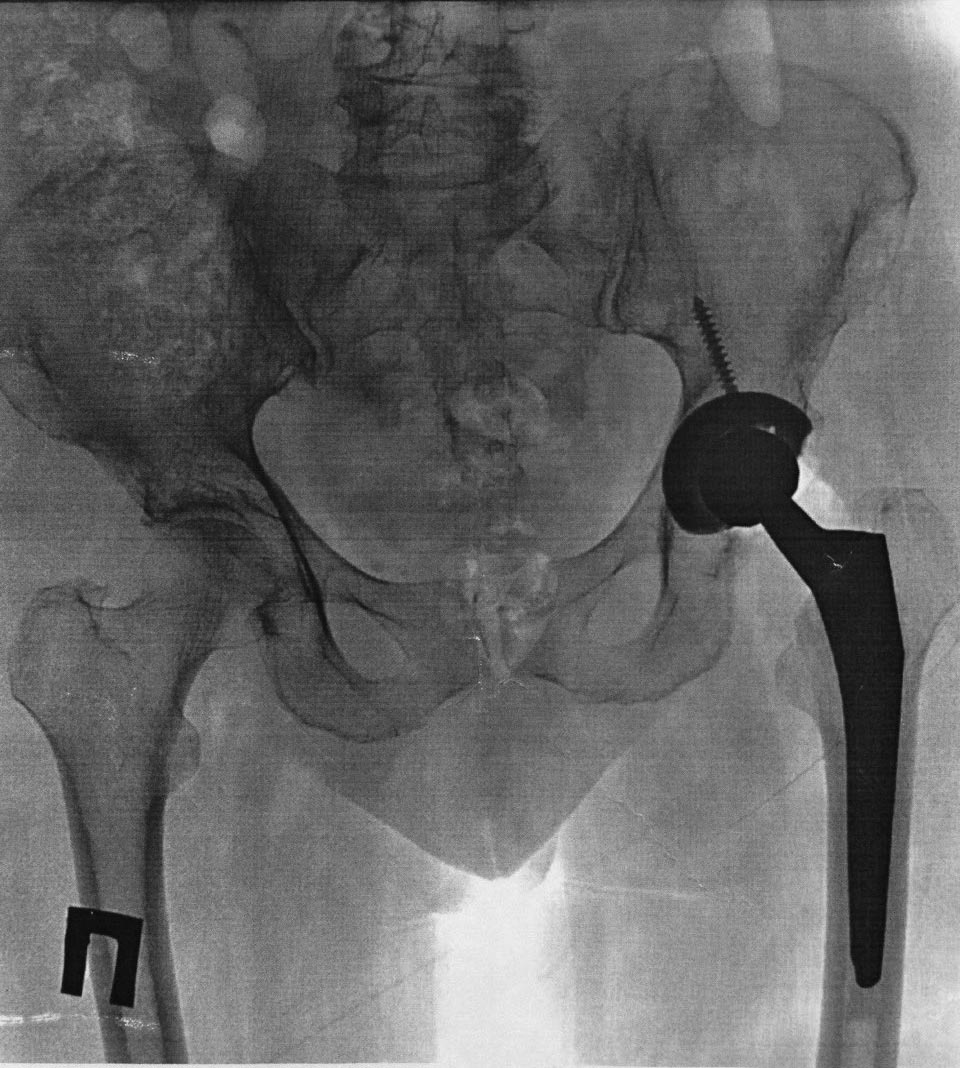

Собственно снимок

Чашка Zimmer Trilogy, ножка Zimmer стандартная Мюллера, цемент synicem 3G с гентамицином

Николай! Сделайте анализы крови на воспаление. Возможно это инфекция. По снимку не похоже на нестабильность элементов. Проксимальный отдел не разрушен, но есть явления локального пороза. Скорее причина его в концентрации нагрузок на дистальный отдел ножки ЭП. Есть выражение у В.Даниляка: увидел пороз ПОБК, сделай ревизию, не жди расшатывания. Думаю, что возможная причина в неврологии. Нужно дообследовать. АИФ

Бедренный и вертужный компоненты клинически стабильны.

Вы имеете ввиду стресс-шелдинг синдром?

вертлужный компонет, как минимум, "вероятно нестабильный", резорбция есть, явных признаков изменения положения нет. Ни о шилдинге ни о байпасе пока речь не идет